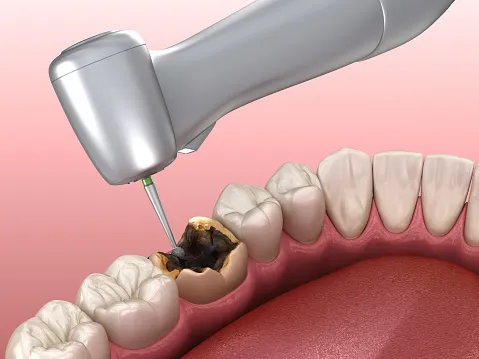

Solution : Composite Filling